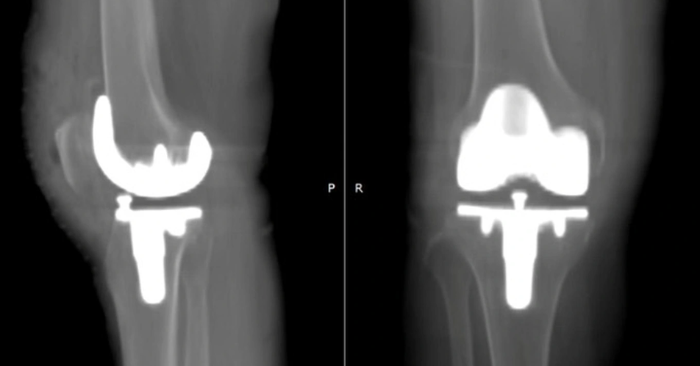

Kết quả sau phẫu thuật cho thấy khớp nhân tạo được đặt cân đối, đúng trục chi và vận hành ổn định. Đặc biệt, chỉ 6 giờ sau mổ, bệnh nhân đã có thể đứng dậy, tập đi với dụng cụ hỗ trợ và tự di chuyển nhẹ nhàng.

Tại đây, ê-kíp bác sĩ đã áp dụng kỹ thuật thay khớp gối có trợ cụ dẫn đường PSI, dựa trên mô hình 3D cá thể hóa. Trước mổ, bệnh nhân được chụp CT để tái tạo hình ảnh 3D của xương đùi, xương chày và toàn bộ trục chi.

Từ dữ liệu này, bộ dẫn đường riêng cho từng bệnh nhân được in 3D, giúp bác sĩ xác định chính xác vị trí cắt xương, lựa chọn kích thước khớp nhân tạo và tối ưu độ chính xác khi đặt khớp.